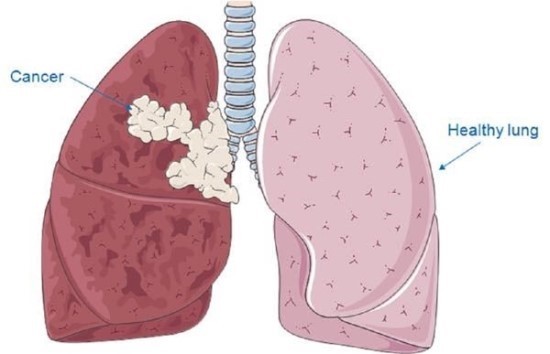

폐렴은 우리의 신체에서 폐, 특히나 산소 교환을 담당하는 폐포에 영향을 미치는 호흡기 질병 중 한 가지다. 이 글에서는 원인, 증상, 치료 옵션 및 관리 조치를 포함해서 폐렴에 대한 포괄적인 정보를 전달하고자 합니다. 폐렴은 폐의 기관인 폐포에 염증이 생기는 질환으로, 주로 바이러스, 세균 또는 기타 감염원에 의해 발생해요.

폐렴 증상 이 염증은 폐포를 침범해서 호흡기계의 기능을 저하시켜요. 폐렴은 모든 연령층에서 발생할 수 있으며, 특히나 어린아이들, 노인, 면역력이 약한 사람들에게 특히나 위험한 질환인데요.

폐렴 원인

폐렴은 박테리아, 바이러스, 곰팡이, 기생충 등 여러가지 요인에 의해 발생할 수 있습니다. 세균성 폐렴이 가장 흔한 유형이며 일반적인 이유는 폐렴연쇄구균과 헤모필루스 인플루엔자입니다. 인플루엔자나 호흡기 세포융합 바이러스(RSV)로 인한 바이러스성 폐렴도 존재한다. 또한 진균성 폐렴은 특정 진균에 노출되어 발생할 수 있고, 마지막으로 드물기는 하지만 기생충성 폐렴도 있습니다.